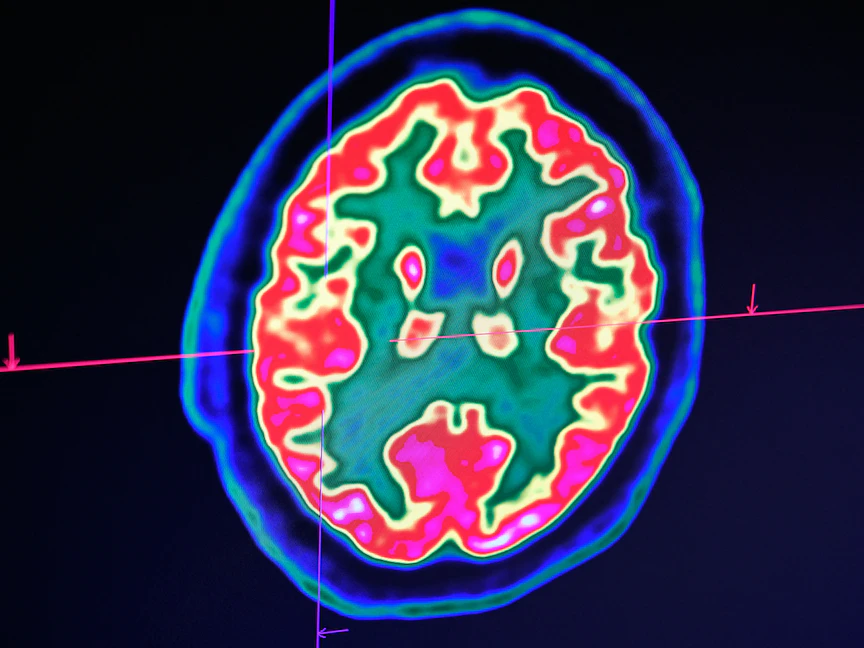

واستخدم الباحثون الرنين المغناطيسي الوظيفي في الدراسة لرصد الإشارات التي تخرج من منطقة المكافأة في الدماغ، والتحكم المعرفي والمرتبطة بقشرة الفص الجبهي، ووجدوا أن تلك المناطق تنشط بشكل أكبر كلما زادت فترة سلوكيات تفقد من وسائل التواصل الاجتماعي.

كما أظهرت مناطق في الدماغ اختلافات في النشاط العصبي طبقاً لعدد الساعات التي ينشطون فيها على مواقع التواصل الاجتماعي.